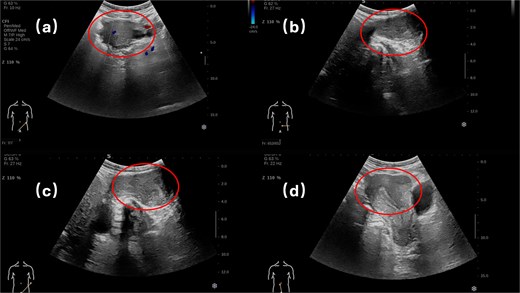

Physical examination revealed a soft, non-tender abdomen without hepatosplenomegaly or shifting dullness; normal bowel sounds were auscultated. A 5 × 5 cm firm, well-circumscribed mass with smooth surface contour and mild tenderness was palpated in the left inguinal region, demonstrating irreducibility and resistance to manual compression. Preoperative imaging modalities—contrast-enhanced computed tomography (Fig. 1) and grayscale ultrasonography (Fig. 2)—suggested a provisional diagnosis of uterine fibroid.

Surgical intervention comprised en bloc excision of the mass with the affected round ligament segment, followed by laparoscopic tension-free mesh hernioplasty (Fig. 3). Histopathological analysis confirmed uterine adenomyoma (Fig. 4). The patient was discharged on postoperative Day 5 following an uneventful recovery.

In this case, the patient exhibited no documented gastrointestinal symptoms—specifically, the absence of abdominal pain, bloating, nausea, vomiting, or alterations in bowel habits—throughout the disease course. Premenopausal menstrual cycles were characterized by regular 25- to 28-day intervals with physiological blood loss. Although adenomyotic lesions are typically estrogen-dependent and tend to regress after menopause, some patients may still experience subtle postmenopausal manifestations such as vague pelvic pressure or discomfort due to residual tissue changes [1]. Notably, this patient demonstrated complete resolution of gynecological symptoms postmenopause, with neither pelvic pain nor abnormal vaginal bleeding or discharge observed. Contrary to expected regression patterns, the left inguinal mass exhibited progressive enlargement, culminating in irreducibility necessitating surgical intervention. Although preoperative imaging likely suggested an incarcerated hernia of uterine fibroid origin, definitive histopathological diagnosis confirmed uterine adenomyoma.